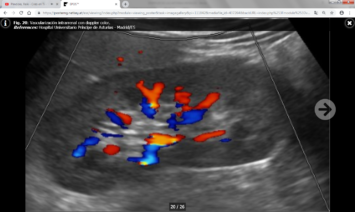

Hay dos grupos de parámetros: Directos o indirectos según se valoren en las arterias renales principales o ramas intrarrenales respectivamente.